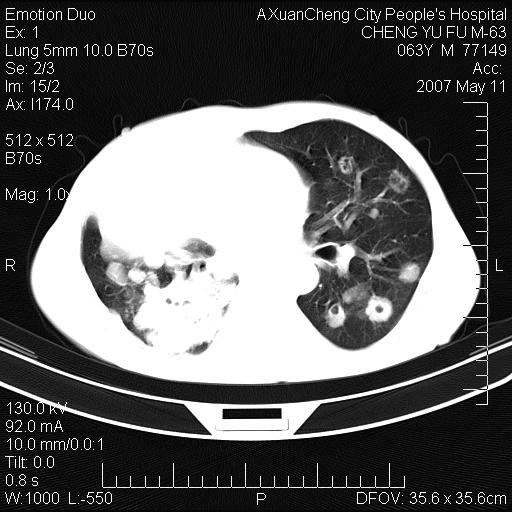

以下是引用小初学者在2007-5-11 19:32:00的发言:[br]1、首先考虑干酪性肺炎支气管播散[br]2、支气管肺泡癌待排

以下是引用zhangzhongshou在2007-5-11 19:30:00的发言:[br]细支气管肺泡癌可能性大。